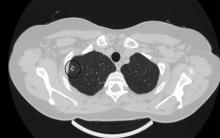

При оценке динамики, я всегда учитываю не только фазы дыхания ( иногда бывает и " на выдохе") , но и фазу самого вдоха (бывает -неполный). Как и в этом случае. Я понимаю, что нельзя писать " существенной динамики не выявлено" . Она есть , или её нет. Учитывая всё это, я высказалась об отсутствии динамики. "Дерево-в-почках" обычно используют при описании инфекционных бронхиолитов (специфических или неспецифических) . Здесь похожее распределение очагов, но если Вы, уважаемые мной коллеги, очень уважаемые, присмотритесь, то увидите, что очаги, как бусинки, нанизаны на септальные перегородки а не в бронхиолах, из чего и следует вывод о саркоидозе. Я тоже решила представитьнекоторые срезы до/после. Обратите внимание на уровень стояния правого купола диафрагмы, который не даёт достоверно говорить о "положительной" динамике. Он явно выше в первом исследовании.

Вот, наример, вроде ничего не "нанизано") мне они напоминают центрилобулярные v-образные узелки. Саркоидоз здесь вполне и очень даже вероятен(полно перилимфатики, о чем Вы и говорите), но нужно исключить сочетание с инфекционным процессом, есть сомнительные элементы. Обратите внимание на стенки верхнедолевых бронхов справа и слева, по мне так справа по-толще будут.

При оценке динамики, я всегда учитываю не только фазы дыхания ( иногда бывает и " на выдохе") , но и фазу самого вдоха (бывает -неполный). Как и в этом случае. Я понимаю, что нельзя писать " существенной динамики не выявлено" . Она есть , или её нет. Учитывая всё это, я высказалась об отсутствии динамики. "Дерево-в-почках" обычно используют при описании инфекционных бронхиолитов (специфических или неспецифических) . Здесь похожее распределение очагов, но если Вы, уважаемые мной коллеги, очень уважаемые, присмотритесь, то увидите, что очаги, как бусинки, нанизаны на септальные перегородки а не в бронхиолах, из чего и следует вывод о саркоидозе. Я тоже решила представитьнекоторые срезы до/после. Обратите внимание на уровень стояния правого купола диафрагмы, который не даёт достоверно говорить о "положительной" динамике. Он явно выше в первом исследовании.

Вот, наример, вроде ничего не "нанизано") мне они напоминают центрилобулярные v-образные узелки. Саркоидоз здесь вполне и очень даже вероятен(полно перилимфатики, о чем Вы и говорите), но нужно исключить сочетание с инфекционным процессом, есть сомнительные элементы. Обратите внимание на стенки верхнедолевых бронхов справа и слева, по мне так справа по-толще будут.